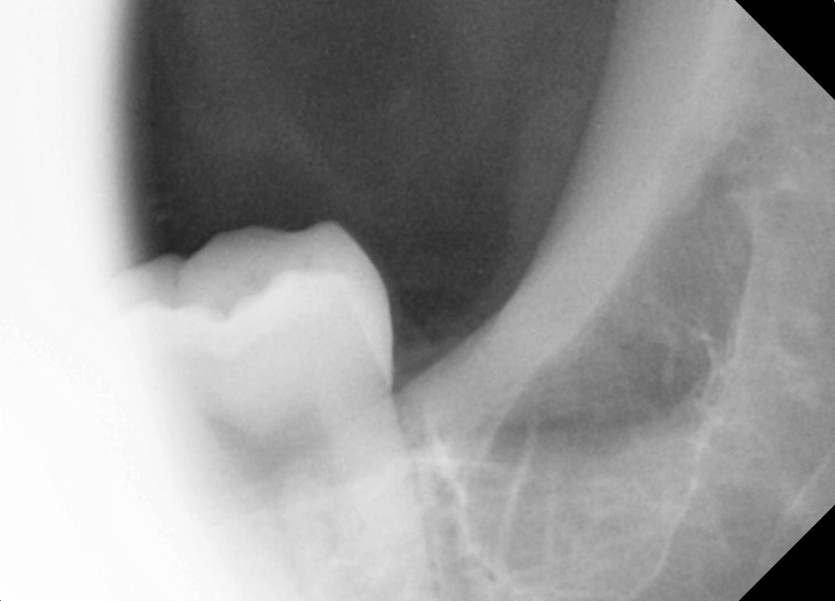

#38,48 사랑니 발치

구강 외과 전문의가 당일 발치했습니다.